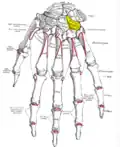

Bones of the left hand. Dorsal surface. Hamate shown in yellow.

Bones of the left hand. Dorsal surface. Hamate shown in yellow. -